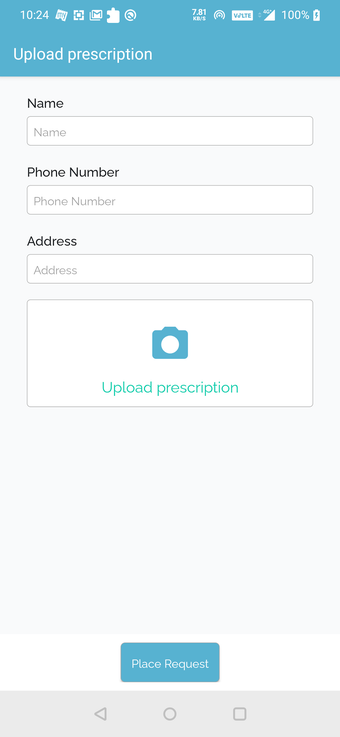

Możesz poprosić ich o wycenę kosztów leczenia lub recepty. Ponadto możesz skorzystać z usług apteki QuickObook. Jeśli pacjent nie ma ubezpieczenia zdrowotnego lub plan ubezpieczenia nie pokrywa kosztów leczenia, zostaniesz o tym poinformowany z góry.